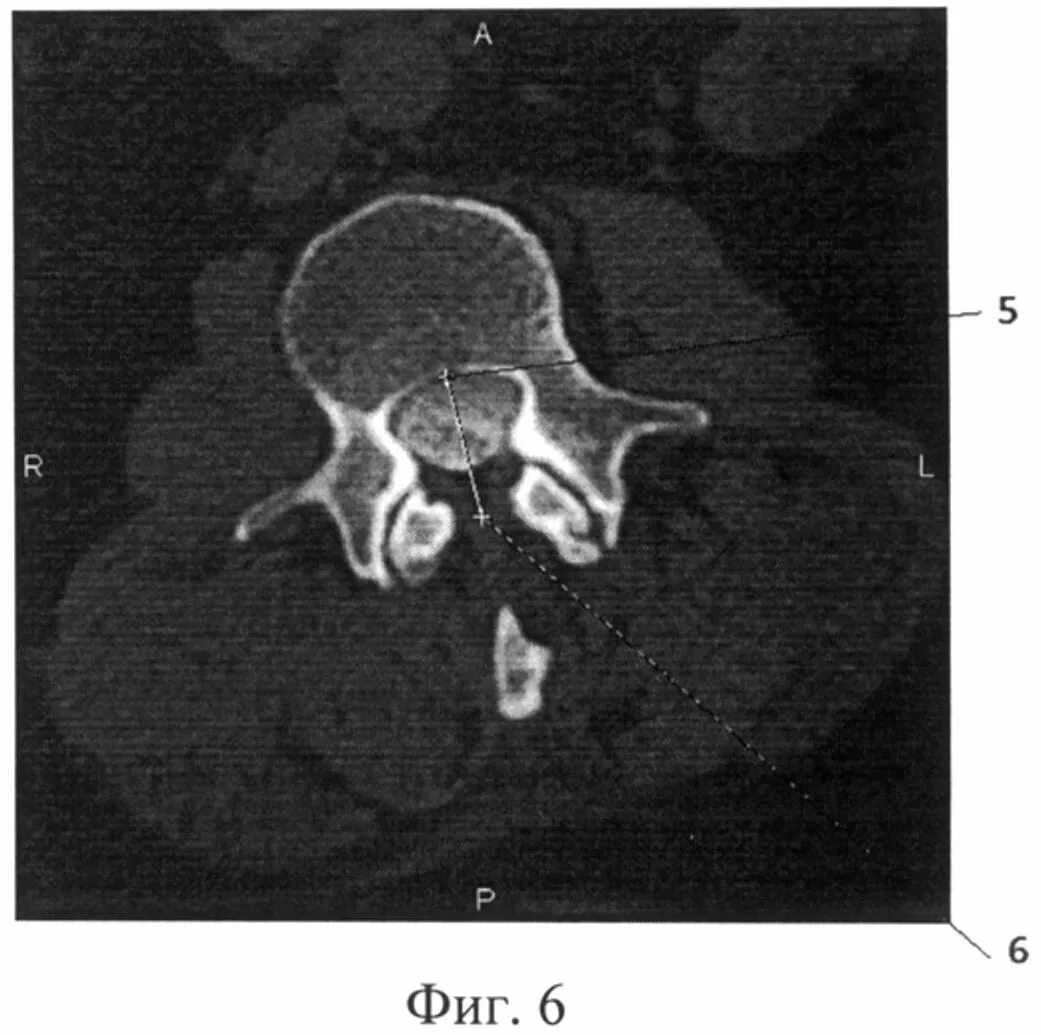

Компрессия дурального мешка что это